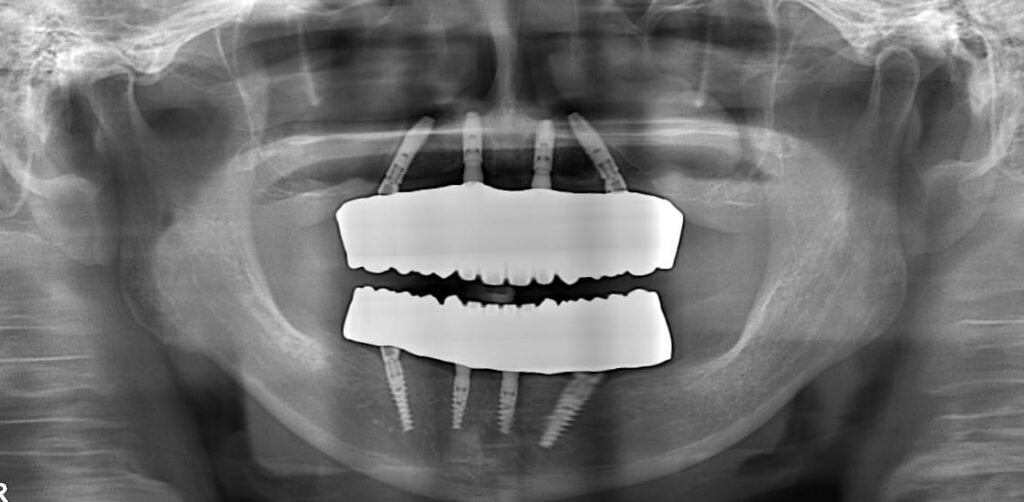

パノラマX線

上顎は残根が数本、下顎は前歯部に残存歯があるが、神経の治療が施されており状態は悪い。

左上顎洞内に粘膜貯留嚢胞が診られる。

パノラマX線写真

Before

After